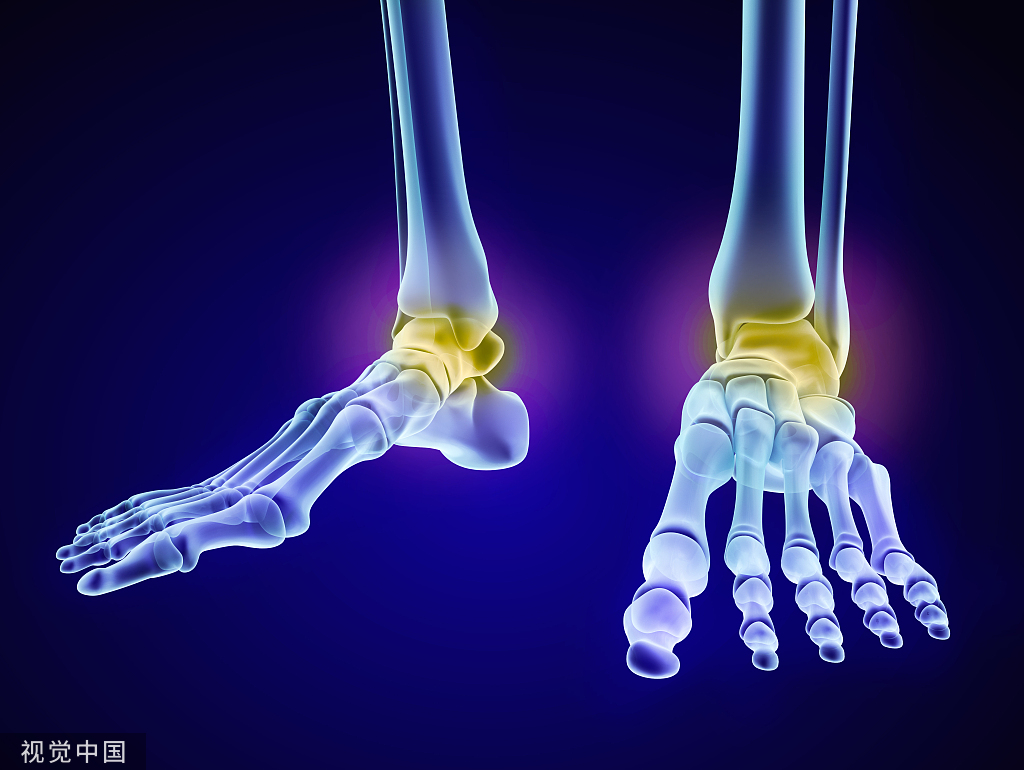

对于外踝撕脱骨折患者,首选的影像学诊断方法是踝关节正、侧位X线片,特殊投照位置包括距腓前韧带(ATFL)位和跟腓韧带(CFL)位可以提高诊断灵敏度(证据质量:3b;推荐强度:强推荐)。

对于可疑外踝撕脱骨折患者,行踝关节 CT检查(证据质量:2b;推荐强度:强推荐);不宜接受CT检查的特殊人群,行踝关节B超或MRI检查(证据质量:2b;推荐强度:强推荐)。